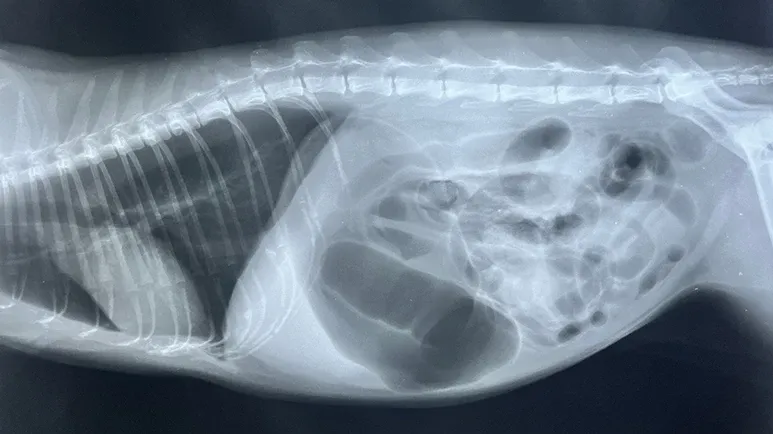

GDV is diagnosed with X-rays. Your dog will first be stabilized with intravenous (IV) fluids and oxygen, and an attempt will be made to move the accumulated gas and fluid out of the stomach. Once your dog is stabilized, she'll undergo anesthesia and surgery to untwist the stomach and tack it to the inside of the abdominal wall in a procedure called a gastropexy.